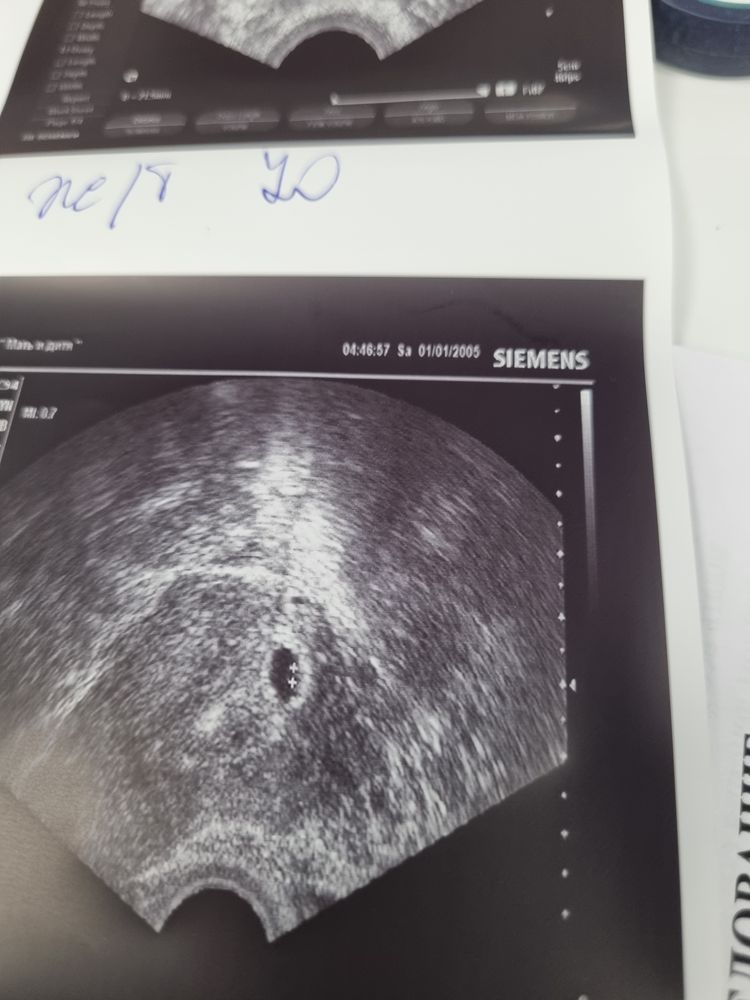

20дпп узи!

Прекрасное плодное яйцо, прекрасный размер! Все отлично идёт! Крепчайте и растите ❤️

Так это прекрасный размер пя, все по сроку у вас❤